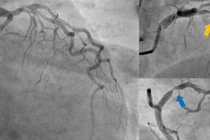

Lọc máu liên tục loại bỏ chất độc và các chất trung gian gây viêm để cứu sống bệnh nhân - Ảnh BVCC

Trước tình huống này, các bác sĩ chỉ định lọc máu liên tục (CRRT - Continuous Renal Replacement Therapy) bằng quả lọc hấp phụ Oxiris, vừa thay thế chức năng thận, vừa hỗ trợ loại bỏ chất độc và các chất trung gian gây viêm. Bệnh nhân được lọc máu liên tục nhiều ngày, kết hợp thở máy, kháng sinh phù hợp, điều chỉnh rối loạn điện giải, kiểm soát đường huyết, hỗ trợ chức năng tim mạch và chăm sóc, theo dõi sát 24/24.